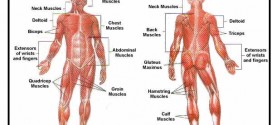

Degeneración del tejido muscular en tejido fibroso. La fibrositis muscular reumática o miofibrosis, es un término médico usado con frecuencia para definir un traumatismo o proceso reumático que desencadena espasmos musculares, con dolor espontáneo, que puede llegar a ser agudo, aunque por lo general se presenta de una manera lenta y persistente. Se caracteriza por una presencia de nódulos difusos …